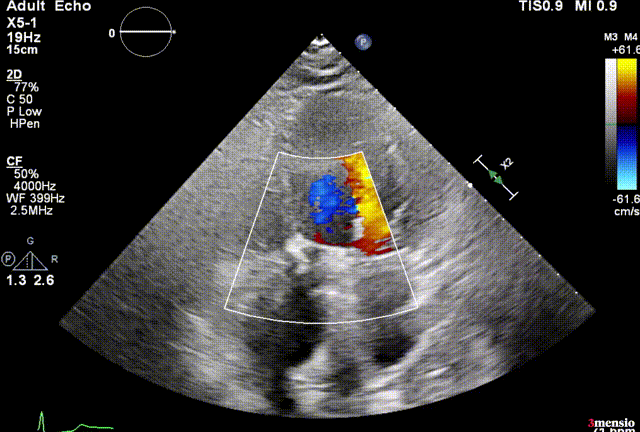

超声提示微量瓣周漏,瓣膜工作良好,最大跨瓣流速2.02m/s,平均压差6mmHg。

输送系统可调弯系统提高了过弓跨瓣的流畅度,术中团队配合默契,操作熟练,成功将瓣膜在最佳位置释放;输送系统进入到撤出仅耗时20分钟。术后即刻心超提示,瓣膜工作稳定,无反流,微量瓣周漏,植入效果理想。